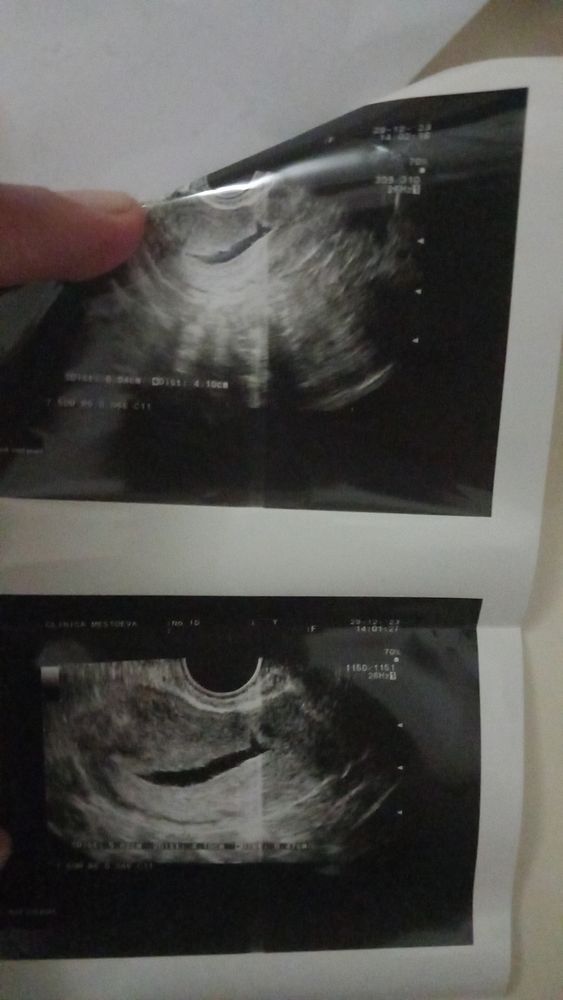

Анна, как класнно. Я очень рада за вас😍 Так вот и я думаю что у меня поздняя овуляция была почему то Вот на фото узи есть что то темное там приувеличении что то было будто кругленькое и длинное она сама не поняла что это. Сказала пойди через неделю. Как думаете и через неделю рано идти даже?

Станислава , я даже незнаю. Почему то кажется что это жидкость. В инете смотрела. А то что на фото если увеличить внутри нее было что то будто прикреплено было с правой стороны от вас чуть яуть длиненькое такой . Она сама поняла что это там поэтому сказала повторим через неделю